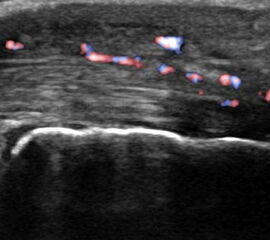

Hier befindet sich ca. 3-5 cm proximal des Tuber calcanei ein als „kritische Zone“ benannter Bezirk, der durch eine ungünstige arterielle Blutzufuhr gekennzeichnet ist (letzte Wiese). Hier finden sich häufig spindelförmige Schwellungen, die bei MRT-Diagnostik nicht selten partielle Nekrosen und Partialrupturen der Achillessehne aufweisen (Abb. 14).

Unabhängig davon können insbesondere chronische Insertionstendinosen der Achillessehne von Partialrupturen (Abb. 15) und erosiven Läsionen des dorsalen Fersenbeines begleitet sein.

Bildgebung

Die sonographische Diagnostik eignet sich primär zur Erkennung schmerzhafter Prozesse im Verlauf der Achillessehne und kann bei Bedarf durch Röntgen bzw. MRT ergänzt werden. Besonders bei längeren Verläufen und kräftigen spindelförmigen Schwellungen (>9mm, Normwert <5mm) im Bereich der kritischen Zone sollte ein MRT zum Ausschluss von Nekrosezonen und Partialrupturen vor Therapiebeginn veranlasst werden. Die sonographisch leicht zu erfassende Veränderung der Sehnendicke im mittleren Sehnenanteil ist ein guter Indikator für die Schwere der Erkrankung und die Beurteilung des Behandlungsverlaufes. Die sichtbaren Veränderungen am distalen knöchernen Ansatz der Sehne sind diskreter.

Insbesondere bei größeren Partialrupturen (Abb. 14) sollten operative Verfahren erörtert werden. Kleinere Partialrupturen sind der ESWT gut zugänglich, wie die beiden nachfolgenden Beispiele zeigen: